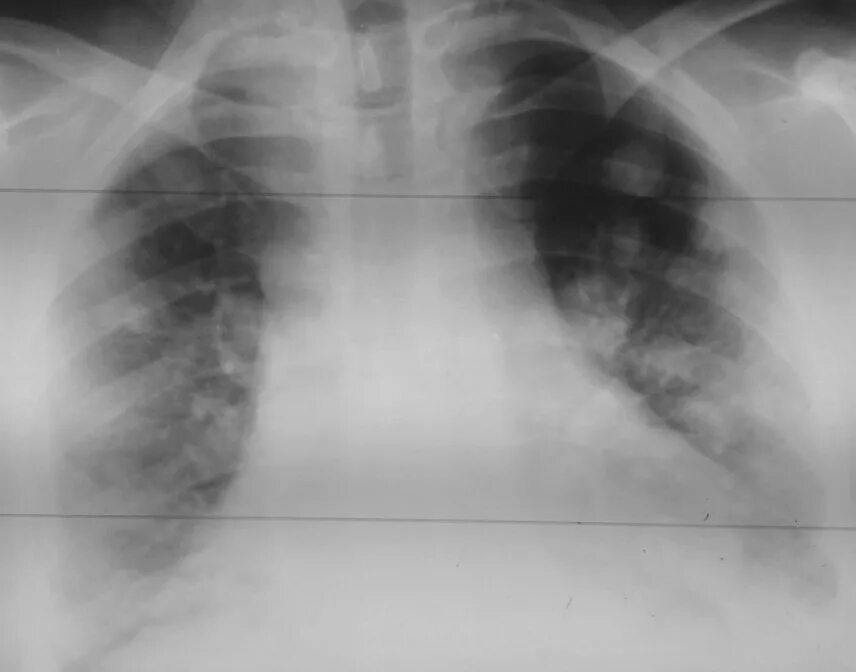

Метастазы в легких терапия